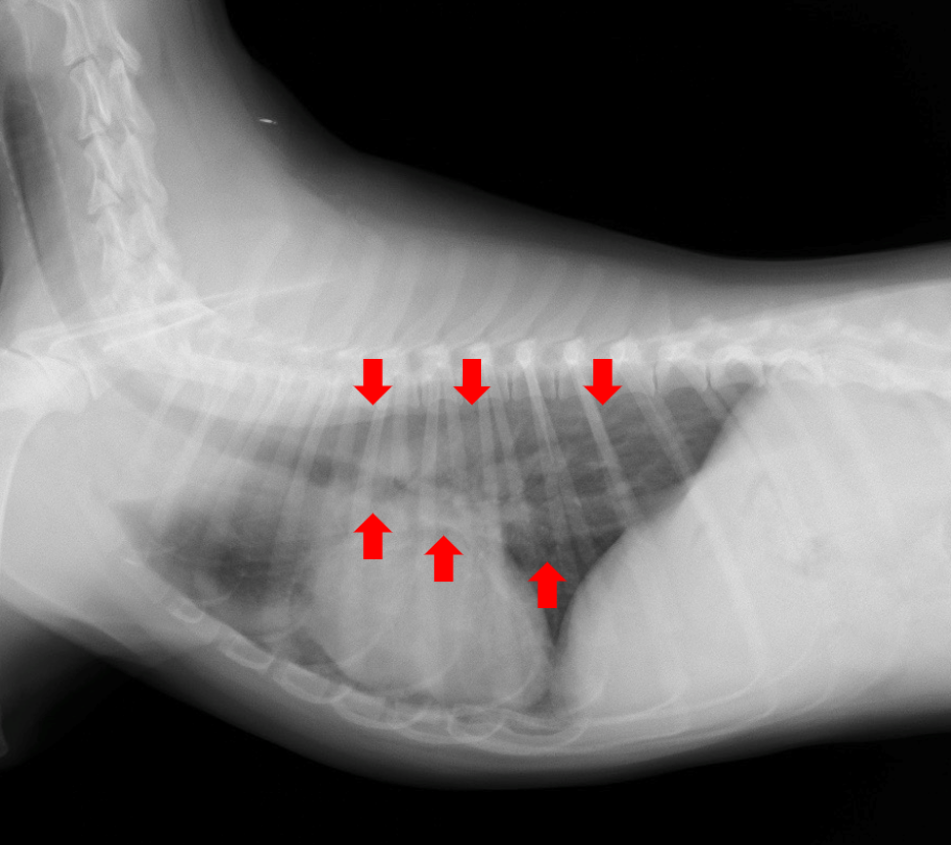

犬の巨大食道症、誤嚥性肺炎どうぶつ病院京都 四条堀川京都市。

食道拡張 巨大食道症 ♢消化器疾患♢院長ブログ。

巨大食道症尼崎の動物病院アニマルプラス。

巨大食道症診療コラム南が丘動物通信南が丘動物病院 兵庫県三田市の動物病院。

犬の巨大食道症草村動物病院 「動物の診察室から」。

巨大食道症宇賀ペットクリニック。